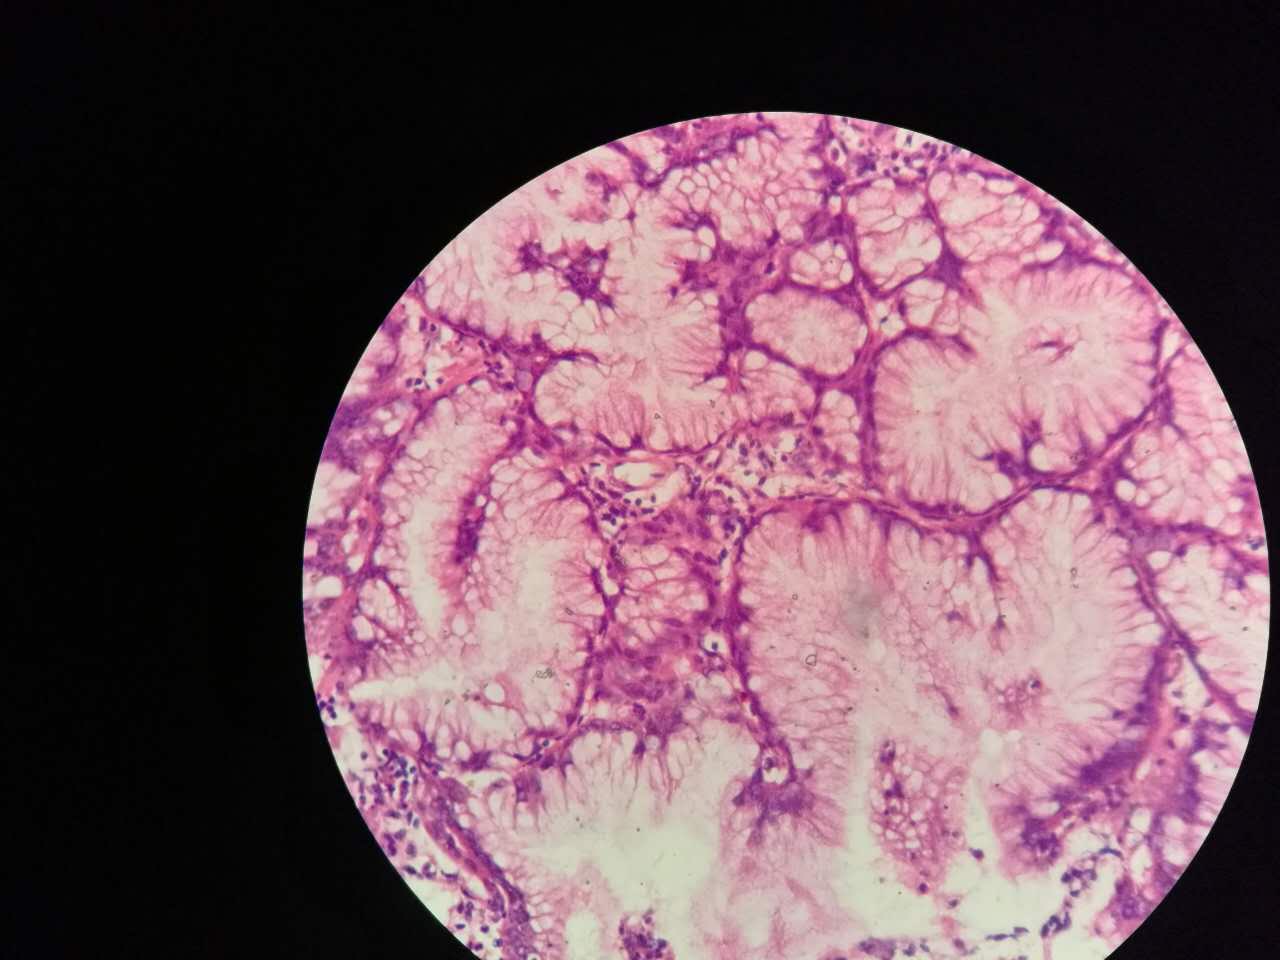

这一幅的上方都是黏液湖

下方是正常肺泡

细胞内白颜色区是粘液,细胞外洋流样的也是粘液(湖)

黏液湖里可以飘着一些细胞,吞噬细胞及肿瘤细胞。

肿瘤细胞飘出去可以种植于肺泡上。

肿瘤细胞堆经常是离开的

中间这一团,整个都是飘过来种植长成这样

这在进展后期特别多见

早期飘散常很近

这个是早期结节状的粘液型腺癌

随着粘液近距离播散

早期粘液漂散也是近距离的,右侧肺泡里干净,没粘液,粘液产量有限,并且互相有黏连牵制。

所以结节性粘液腺癌边界一般较清楚